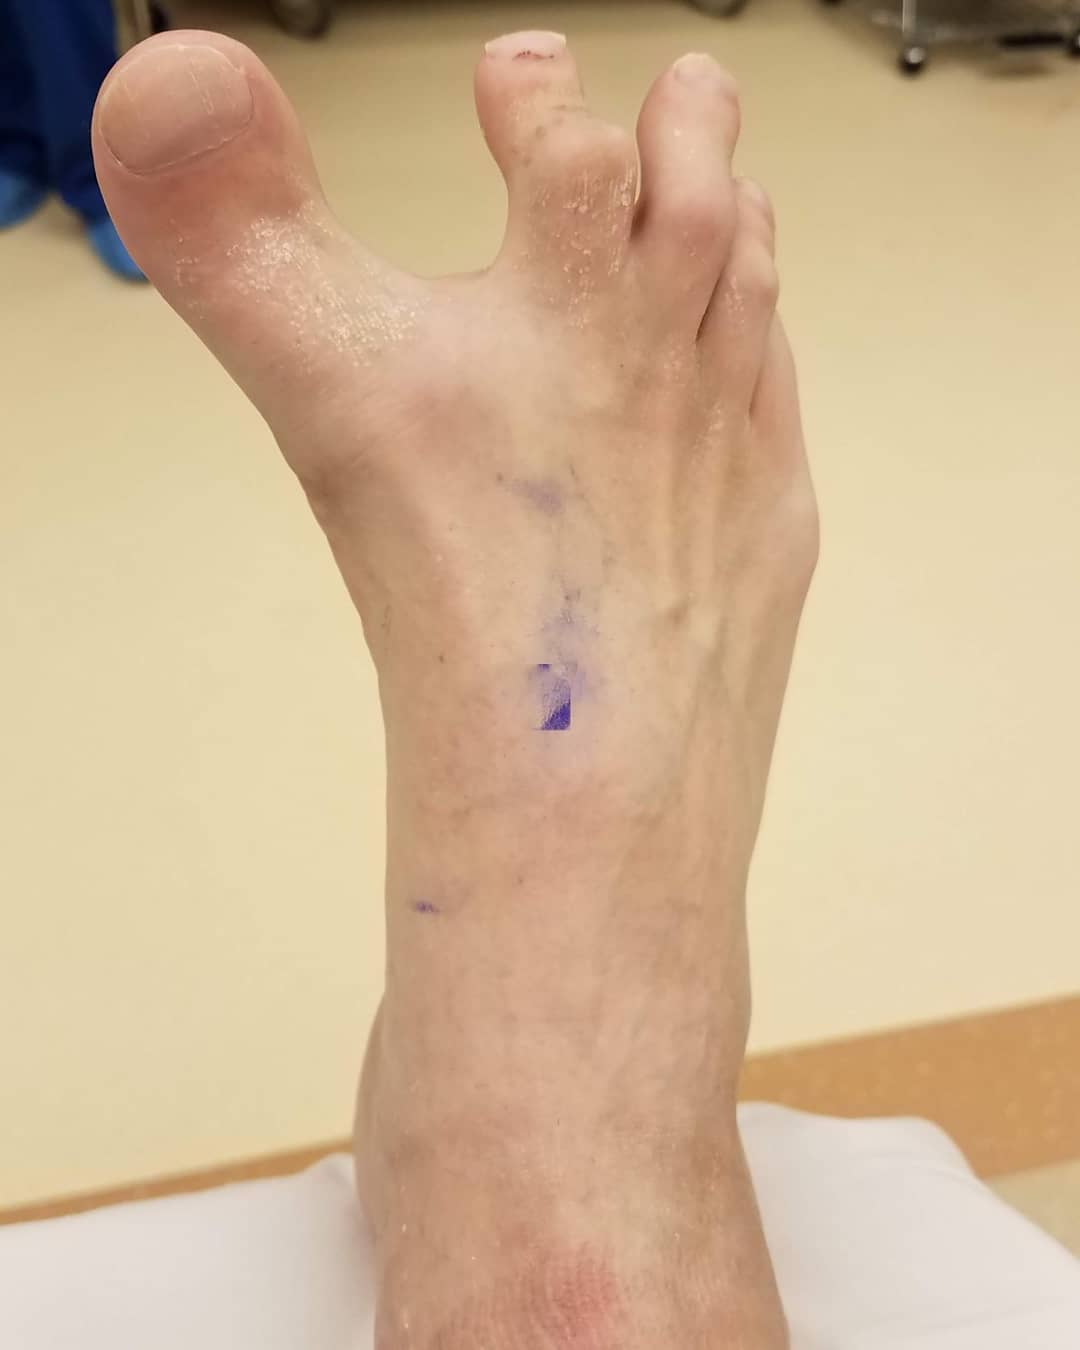

The foot is arguably the most complex part of the skeletal system with 33 joints, 26 bones, and more than 100 ligaments, tendons, and muscles.